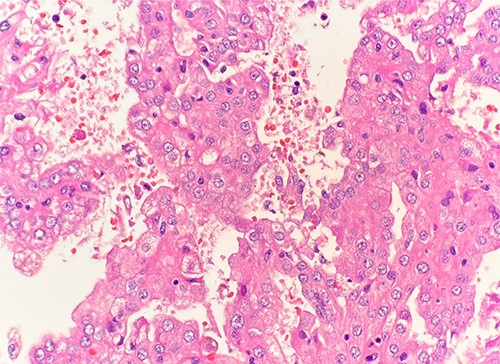

Microscopic examination revealed that clear cell RCC (Fig. 1), papillary RCC type 1 (Fig. 2), and papillary RCC type 2 (Fig. 3) were present in the right kidney, and papillary RCC type 2 was present in both kidneys. Immunostaining showed that tumor cells were positive for alpha-methyacyl-CoA racemase (Fig. 4), CD10, CK7, and vimentin, and negative for CD117.

Microscopic examination reveals small cuboidal cells arranged in a single layer on papillary cores. HE stain 40x.